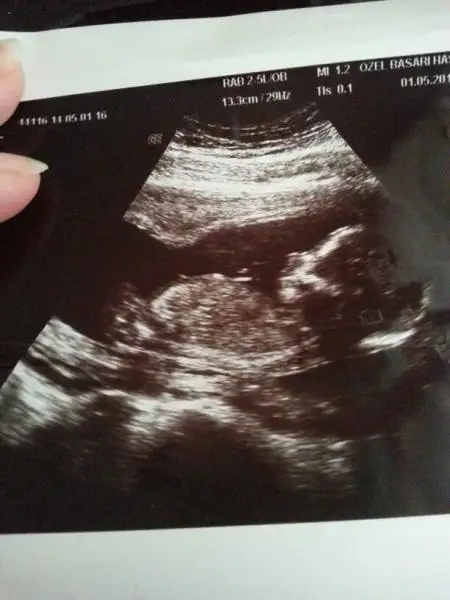

resim 1

Eki Görüntüle 473828 gordugunuz gibi ust taraftaki simgedende anlasildigi gibi eger cikinti paralel ise kiz

yok 30°lik bir aciyla yukari dogru bakiyorsa %99 oglunuz olacak demektir simdi bi kac ornek resimler daha koyacagim kiziminkide dahil